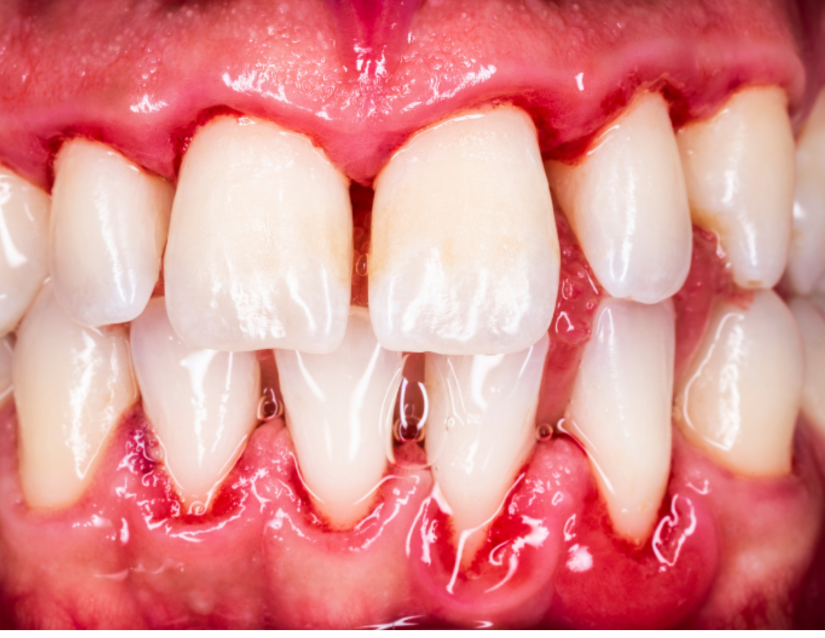

Cirugía para la eliminación de bolsas infecciosas

Rescatando dientes en riesgo de movilidad

Si la infección ha creado espacios profundos (‘bolsas’) entre el diente y la encía donde las bacterias se esconden, es necesaria una intervención correctiva. Accedemos a estas zonas difíciles para limpiarlas a fondo y reducir la bolsa, creando un entorno que tu cepillo sí pueda limpiar y evitando la pérdida del diente.